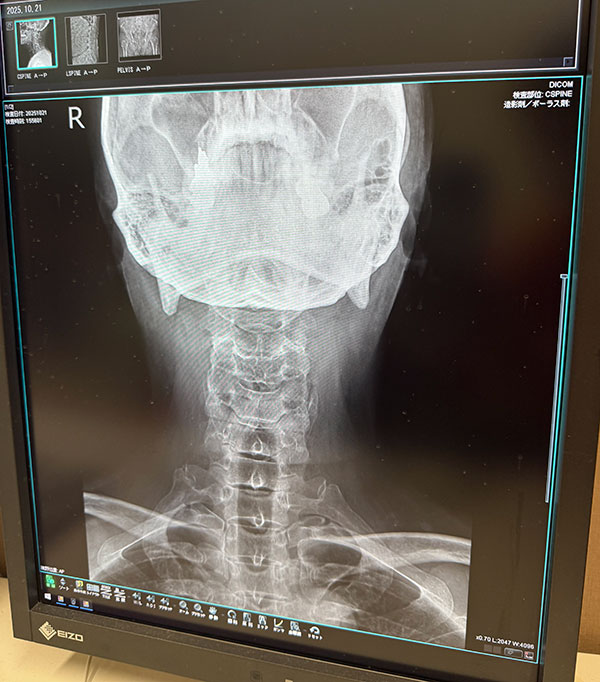

| 2025/10/21火 楓の森で検査 ↓前 次↑ 朝イチ女王送ってクルっとひさ枝へ。 ![]() 8:30ぐらいですが少し落ち着いてきたのかな。 ![]() 姉やんから頼まれたお土産うどん買いがてらでしたが久々釜玉かけを。うむ、自分にとってのこの店はやっぱこれやな。 ![]() 主治医モリケン先生のトコにも行きます。受付の美女に「いつもの膝ですか?」→「はい、それに加え腰と尻と首と。。」→「事故か何かで?」→「いや転んだと言うか。。」→「いつですか?→「10/18土です」てか 「先生も知ってますので」 ※その場にいたw というやりとりをしました!レントゲン撮ってもらいました。 ![]() ドキドキしながら結果を。 ![]() 首は一箇所狭まってるそうで、今回のが原因ではなく加齢とのこと。ヨシキよりかはマシでしょう。 ![]() ヒビ等はないようです。 ![]() 椎間板はもうすぐヘルニアかもやけど、それは元々やからなあ。 ![]() パイプ椅子で頭打ったけどそれなかったらもっとヤバかったかもとのことでした、ともかくHOTしつつ 正式に椅子アクションを禁止 ※ジャンプもデス されました。新しい面白いコトを探しましょう。 ![]() いつもの膝ヒアルロン酸デュアル打ってもらって後に。 ![]() ひさ枝でもらった麺で寄せ鍋ですか。 ![]() 土曜のライブや日曜からの九州出張までに痛さマシになってて欲しい。 ↓前 次↑ | ||